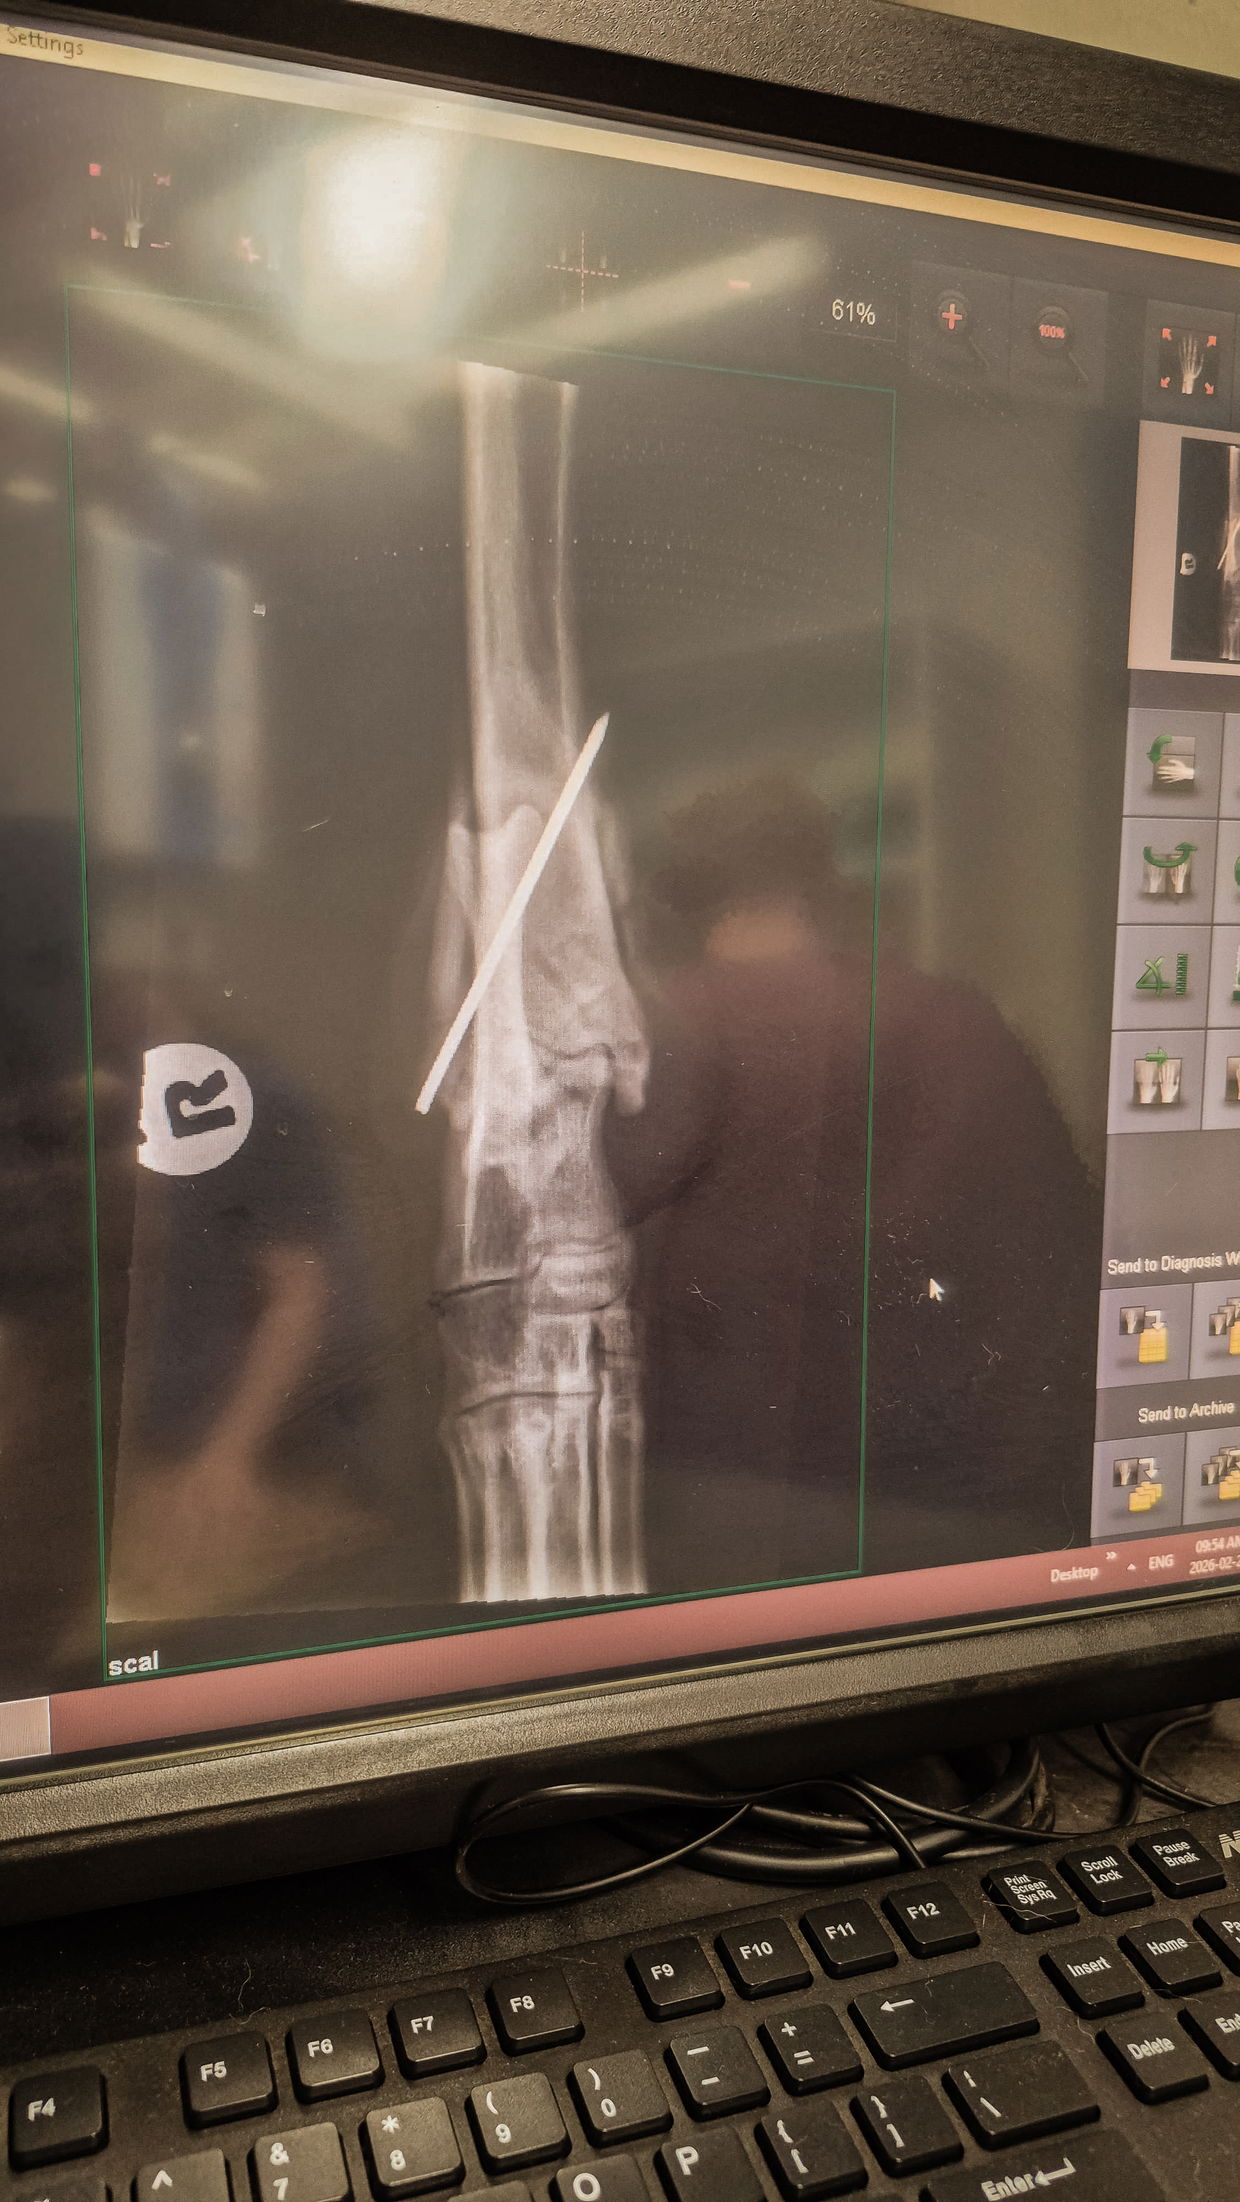

On 3 February, Zuko was sedated for X-rays. The results immediately changed the tone of the situation. The scans revealed fracture areas near the joint - not a simple injury, but one with potentially severe consequences. The clinical realities were distressing: preserving full function of the leg would require specialist intervention. Without it, the alternatives included amputation, or in a worst-case scenario, euthanasia.

On 11 February, he travelled to Vetscape Animal Hospital in Paarl. There, a CT scan provided a clearer understanding of the injury: a distal tibia fracture just above the tarsal joint. Under the care of specialist surgeon Dr Charlie Boucher, the fracture was stabilised using a cross-pinning technique - the most appropriate solution given the nature of the break.